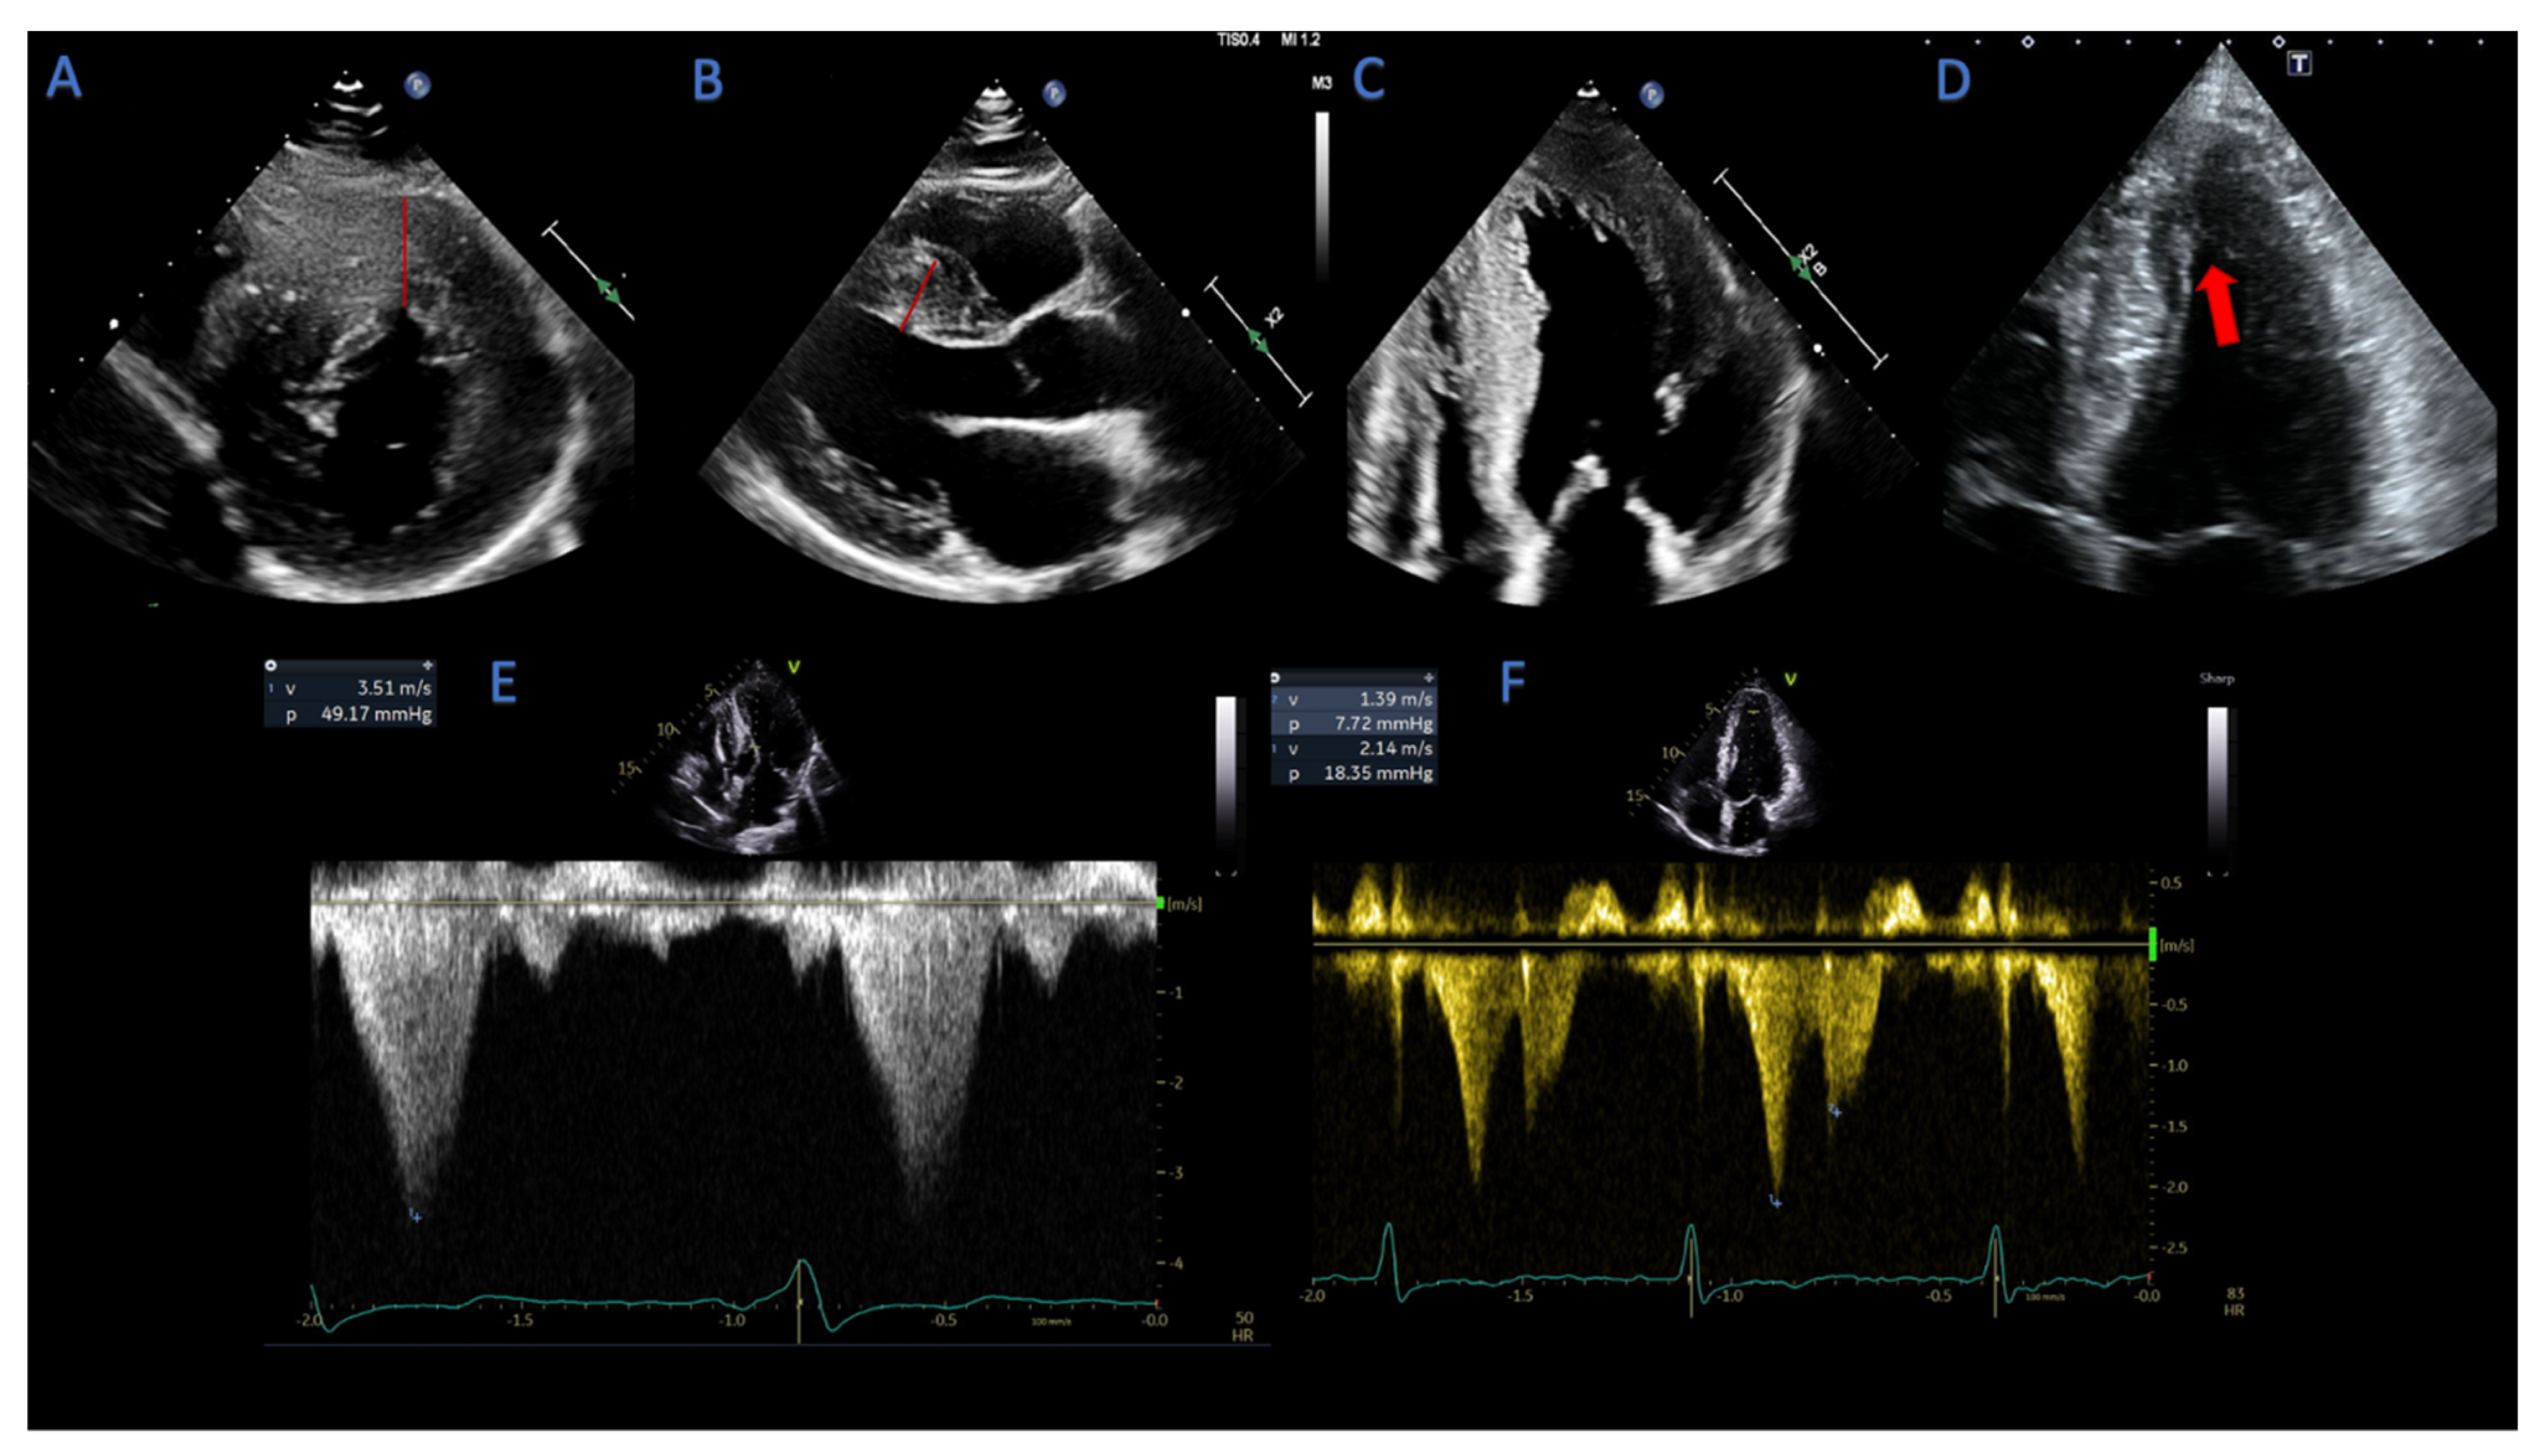

2.1.4. Assessment of LVOT- and Mid-Cavity Obstruction

2.1.5. Mitral Valve Abnormalities in HCM Patients